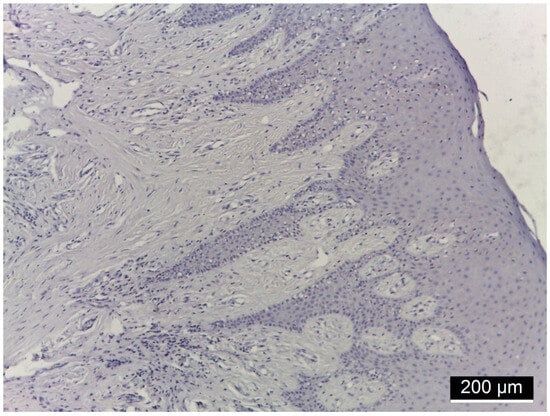

| Patients Number | Diagnostic | Immunoreactivity Intensity MMP-14 | ||

|---|---|---|---|---|

| Membranous | Cytoplasmatic | Nuclear | ||

| 9 | Diabetes mellitus + Periodontitis | + | − | − |

| 7 | Diabetes mellitus + Periodontitis | +++ | − | − |

| 10 | Periodontitis (control) | + | − | − |

| 7 | Periodontitis (control) | − | − | − |

| Location | IR Intensity | DM + PD n = 16 | PD n = 17 | Chi Square Test p |

| MMP-14 | ||||

| Membranous | (−) (+) (++) (+++) | 9 (56.2%) 7 (43.8%) | 7 (41.2%) 10 (58.8%) | 0.004 0.883 nc 0.002 |

| Cytoplasmic | (−) (+) (++) (+++) | 16 (100%) | 17 (100%) | 1.000 nc nc nc |

| Nuclear | (−) (+) (++) (+++) | 16 (100%) | 17 (100%) | 1.000 nc nc nc |